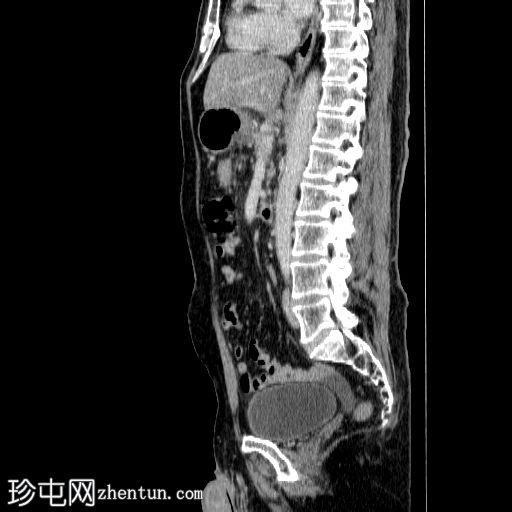

矢状C+动脉期

6.jpg

胰体尾弥漫性增大,特征为胰腺实质低强化,无明显坏死区域。

该病灶与以下表现相关:

胰周筋膜平面边界不清的污迹,无明显壁形成、气室、固体碎片或血液产物。

病变横向延伸至左前肾旁间隙,伴有Gerota筋膜增厚。

病变向下延伸至盆腔。

无肠系膜或脾脏血管阻塞的证据。

未见导管扩张或钙化。

在疾病早期,可能出现胰腺肿大、胰腺组织低增强、胰周脂肪条带、积液和筋膜增厚。